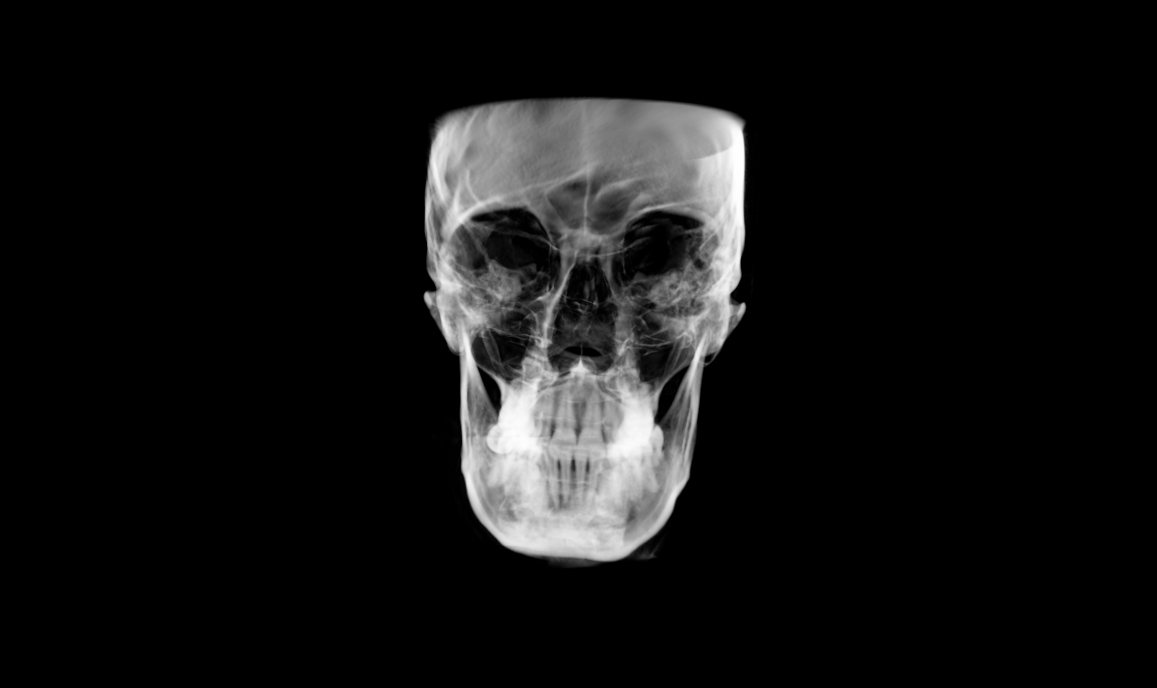

• Face Focused Initial Assessment

CBCT:

Assessment:

Chief Complaints

Bite, TMJ issues, appearance of jaw

Signs & Symptoms

Clinical Exam Conditions

• Head Posture: Forward Head Posture

• Facial Features: Allergic Eye Shiners, Excessive Buccal Corridors

• Vertical Upper Jaw Position: Mild Vertical Maxillary Excess

Assessment